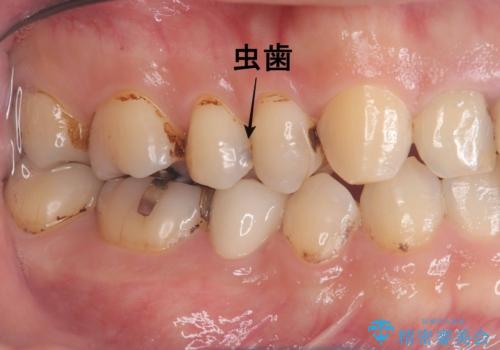

- CRの下が虫歯になっており歯が欠けている状態でした。古いCRと虫歯を除去しセラッミクインレーで治療しました。

CRが劣化し虫歯になり欠けている状態でした。歯を長持ちさせるために(再治療を減らす)セラッミクインレーで治療を行いました。

右上4のCRも劣化していてかつ形態も良くないので治療の必要性はご説明させていただきました。